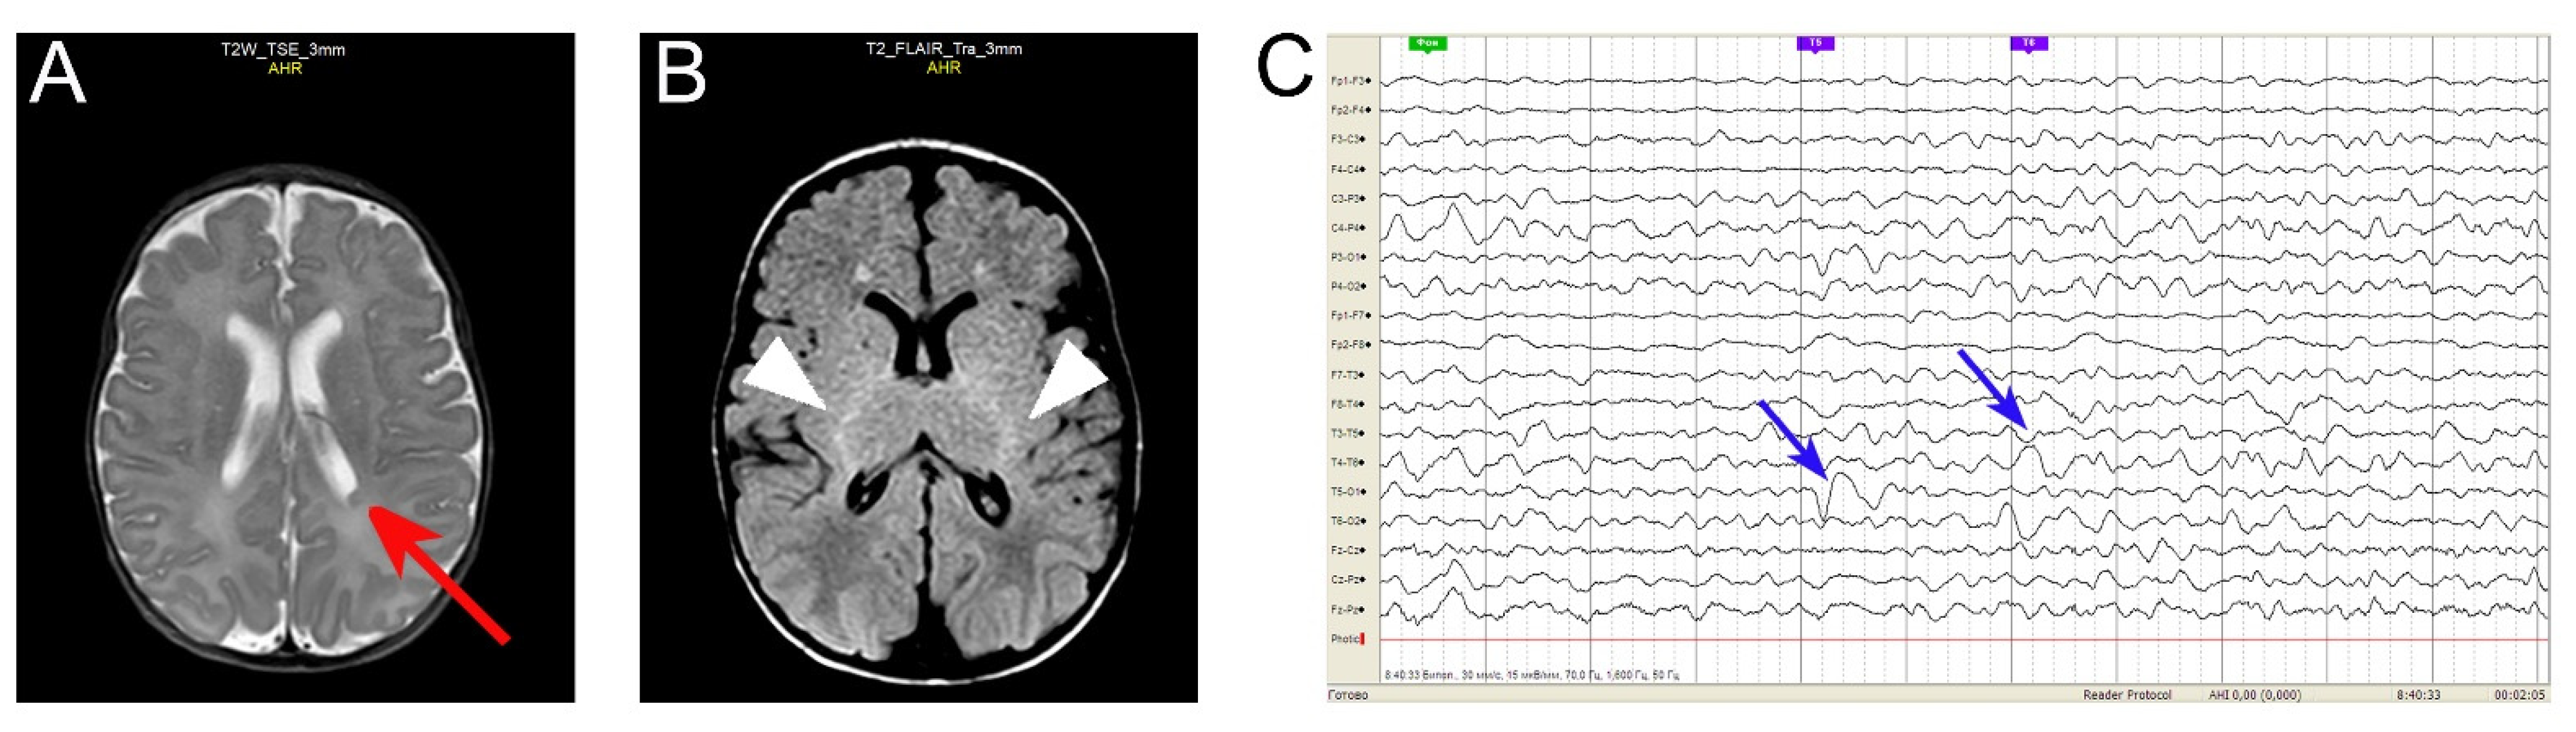

This male Russian infant (currently 2 years old) displayed severe, early-onset developmental and epileptic encephalopathy (see Figure 1, Supplementary Table S1). Following the informed consent, whole-exome sequencing revealed a hitherto undescribed Gln52Arg (c.155A > G) heterozygous mutation in exon 2 of GNAO1. Predictive algorithms following ACMG criteria [31] characterize the mutation as likely pathogenic; no other pathogenic mutations were identified (data not shown). Sanger sequencing confirms the mutation (Supplementary Figure S2A). As both parents do not harbor the mutation (Supplementary Figure S2B,C), the GNAO1c.155A > G (Gln52Arg) is concluded to be a de novo mutation. The clinical manifestations of this hitherto undescribed de novo Gln52Arg mutation in GNAO1 are reminiscent of the previously observed Gln52Pro mutations in GNAO1 and in GNAI1 [23,24]. Table 1 provides a comparison of the clinical features of the three patients with mutation in the codon Gln52.

Recently, a number of mutations in a related gene GNAI1, many of them identical to those in the GNAO1-encephalopathy (Supplementary Figure S1), have been described to cause similar clinical manifestations in children [23]. Among the amino acids found mutated both in the GNAO1- and GNAI1-encephalopathy, the Gln52Pro mutations have been identified [23,24]. Here, we describe a hitherto unknown Gln→Arg mutation in the same site of GNAO1. The infant suffers from a combination of developmental delay, hypotonia, and seizures, accompanied by mild structural brain abnormalities (Figure 1). Although epileptiform discharges may be due to the periventricular nodular heterotopia (PVNH), the severity of the developmental outcome of our patient cannot be explained by this focal neuronal migration defect alone and is rather expected to result from an abnormal brain development related to the GNAO1 variant. Brain MRIs are usually normal in GNAO1-related encephalopathies, and the discovery of a PVNH might be coincidental (although we cannot exclude a possible link with the genetic variant); that needs to be confirmed with further studies.

Figure 1. Brain MRI and EEG of the GNAO1 Gln52Arg patient. (A,B) Brain MRI ((A): axial T2 weighted sequence, (B): axial FLAIR) reveal left posterior periventricular nodular heterotopia (PVNH, arrow in (A)) and hyperintensity of the posterior limb internal capsulae (arrowheads in (B)). (C) EEG reveals left posterior temporoparietal slowdowns (arrows).